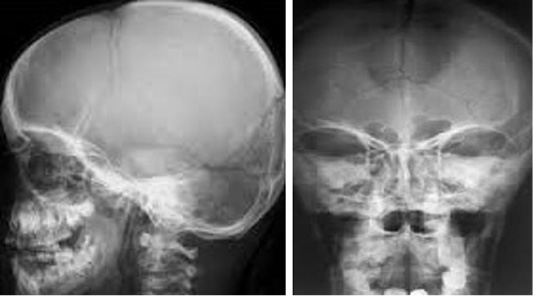

Figure 3

Shows normal; b) abnormal skull with CCD